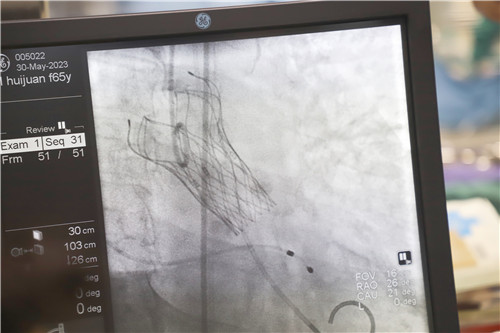

不為良相,便為良醫(yī)。石化醫(yī)院心血管內(nèi)科團(tuán)隊(duì)在汪念東副院長的帶領(lǐng)下和皖南醫(yī)學(xué)院弋磯山醫(yī)院湯圣興教授的指導(dǎo)下,術(shù)中利用豬尾管懸吊AL1導(dǎo)管增強(qiáng)同軸跟進(jìn),經(jīng)過多學(xué)科四個(gè)小時(shí)的緊張救治,最終建立軌道成功置換瓣膜。

王女士術(shù)前測壓力階差高達(dá)110mmHg,在置換瓣膜后,壓力階差恢復(fù)到5mmHg,且無瓣周漏,在麻醉蘇醒后恢復(fù)了自主心率和自主呼吸。